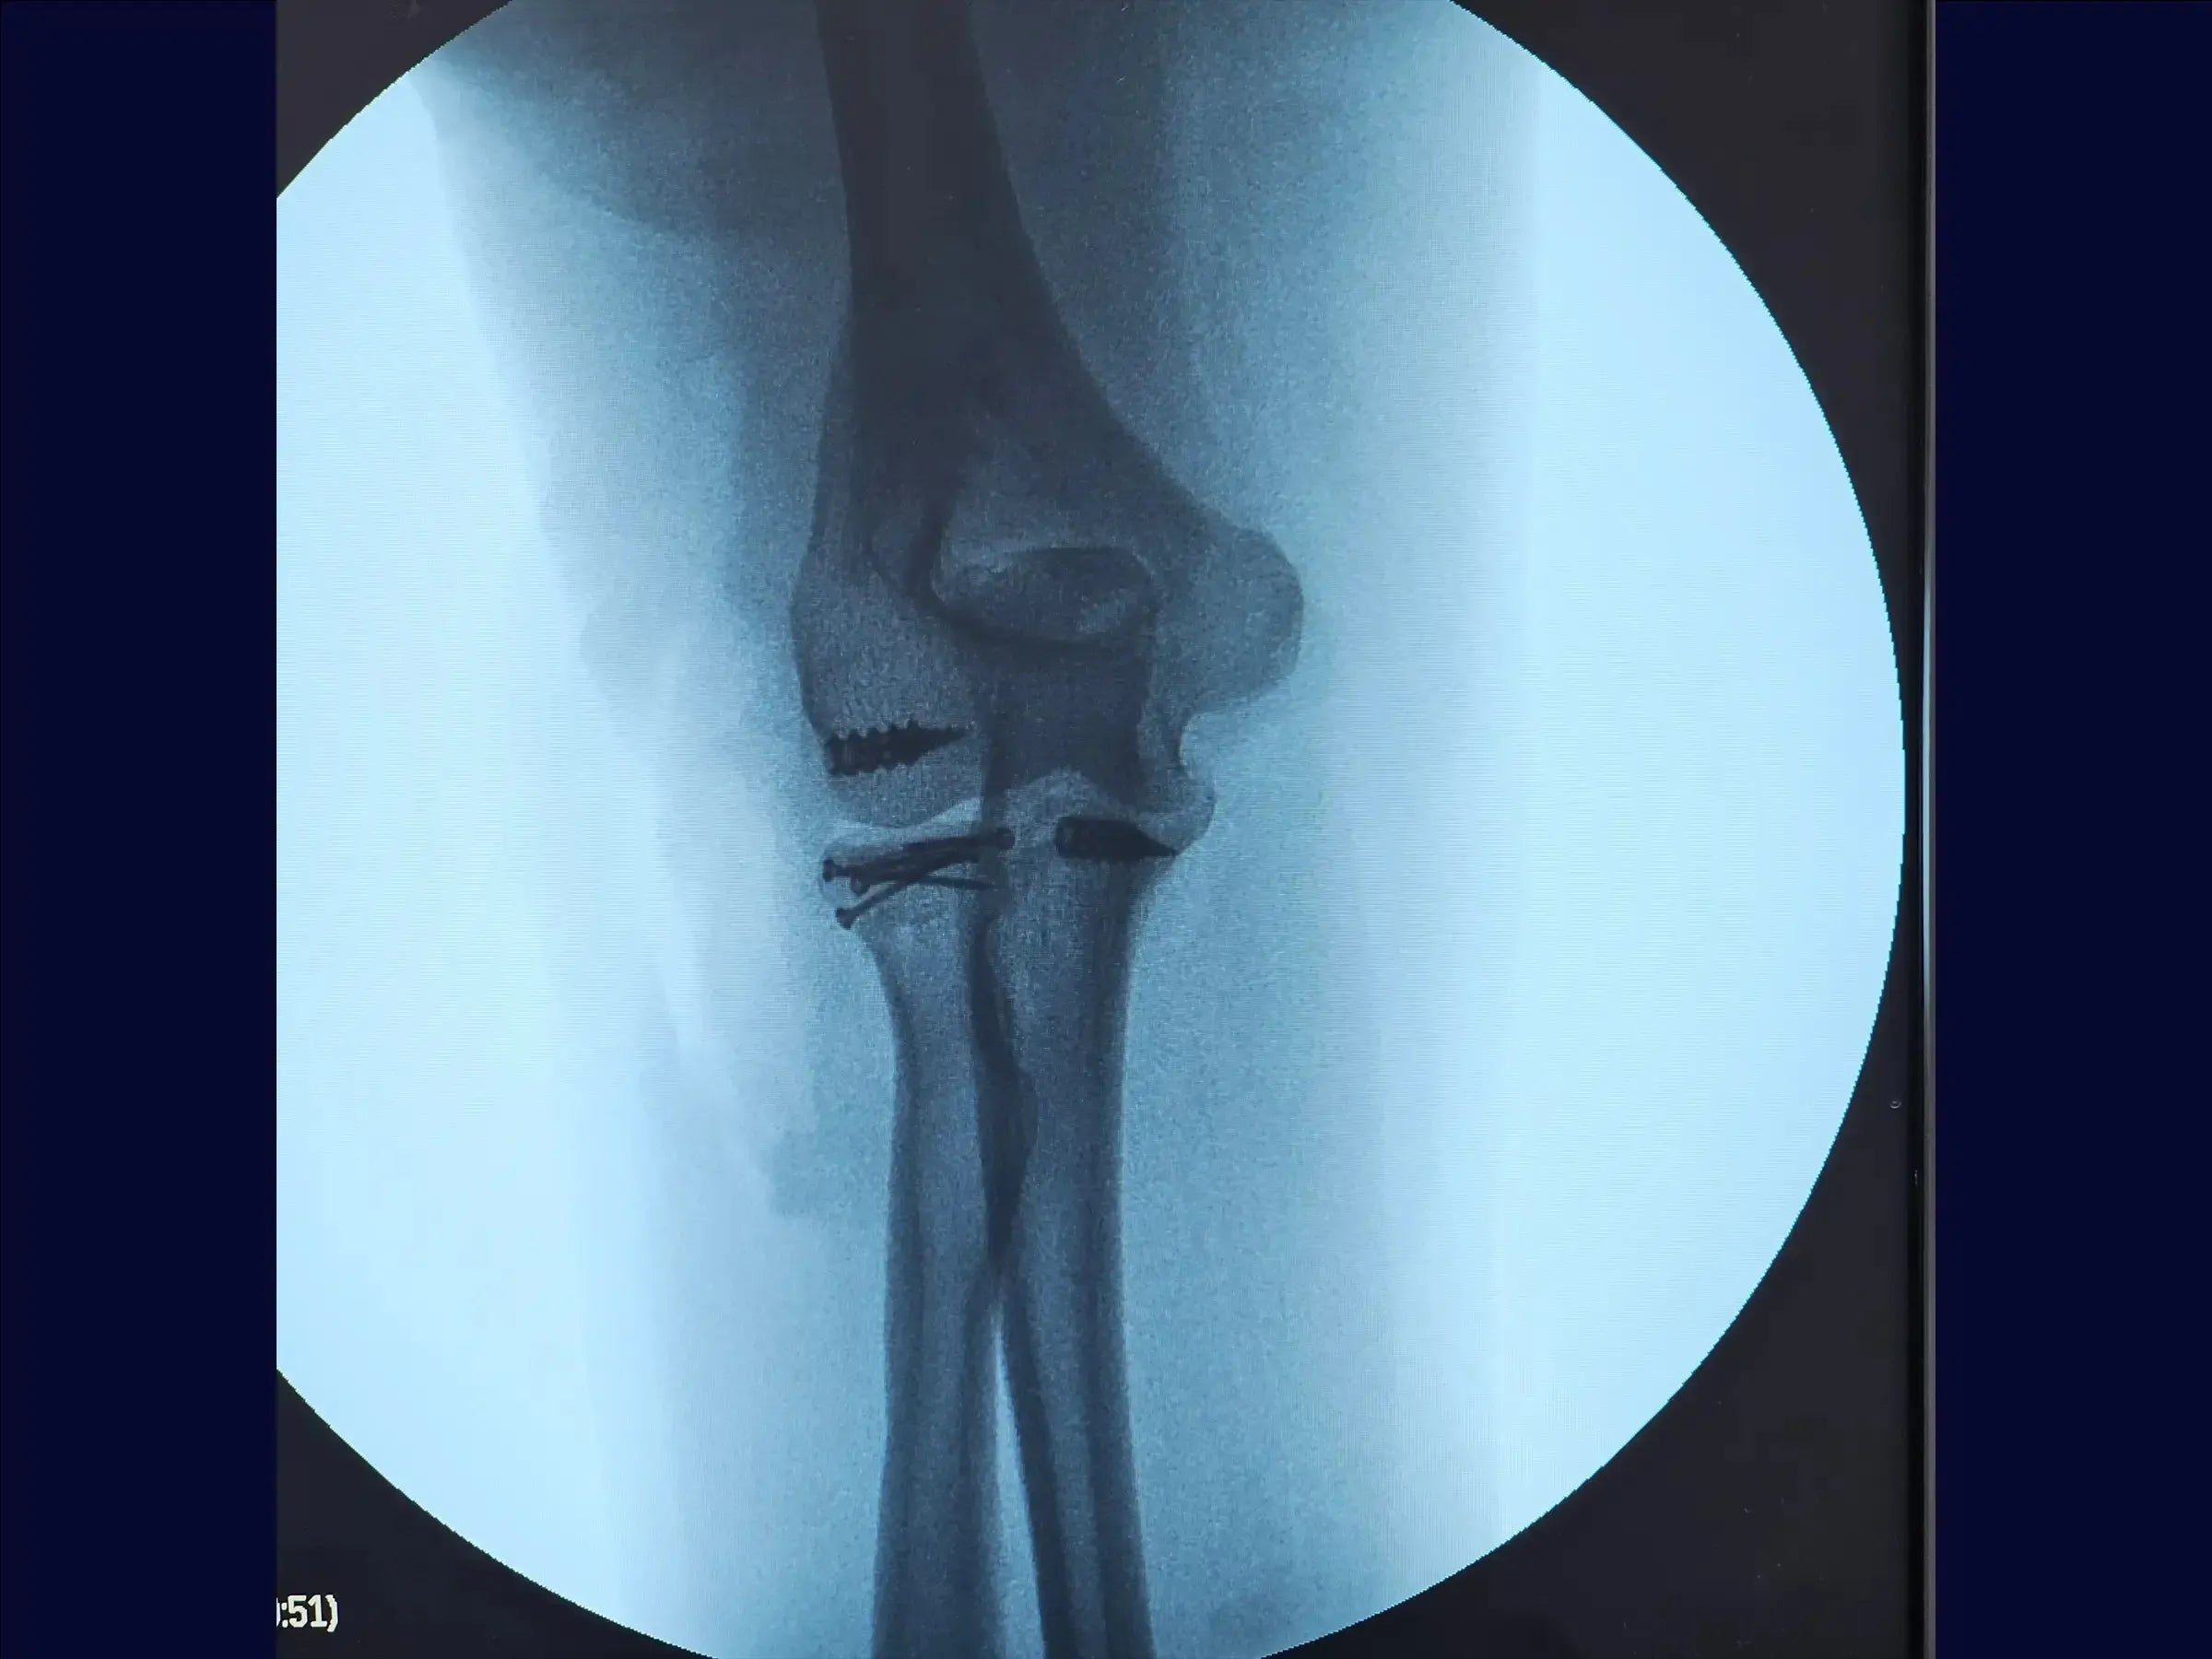

- Síntesis de cabeza radial Osteoss : utilizar tornillos de 1,5 mm, paralelos o divergentes, sin cruzar, para una fijación subcondral estable .

- Reparación del proceso coronoideo y la cápsula: utilice un ancla de metal de 5,0 mm y suturas de alta resistencia para suturar firmemente la cápsula articular anterior.

- Reparación del ligamento lateral: reinsertar el ligamento con ancla y ajustar con valgo para asegurar una tensión adecuada.

- Cierre y Prueba: Cerrar por planos y verificar el rango de movimiento intraoperatorio , asegurando la ausencia de bloqueos.